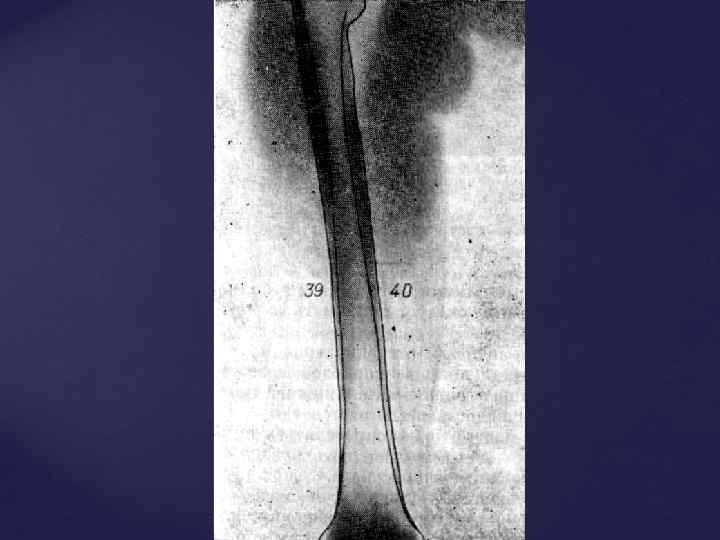

1. Форма кости - а) трубчатые Б) губчатые В) плоские 2. Структура кости: а) компактное вещество Б) губчатое вещество Описываются : - отделы кости, - костно-мозговой канал - зона роста (толщина метаэпифизарного хряща) - суставные концы, рентгеновская суставная щель - контуры кости Принципы изучения Rграмм костей и суставов

1. Форма кости - а) трубчатые Б) губчатые В) плоские 2. Структура кости: а) компактное вещество Б) губчатое вещество Описываются : - отделы кости, - костно-мозговой канал - зона роста (толщина метаэпифизарного хряща) - суставные концы, рентгеновская суставная щель - контуры кости Принципы изучения Rграмм костей и суставов